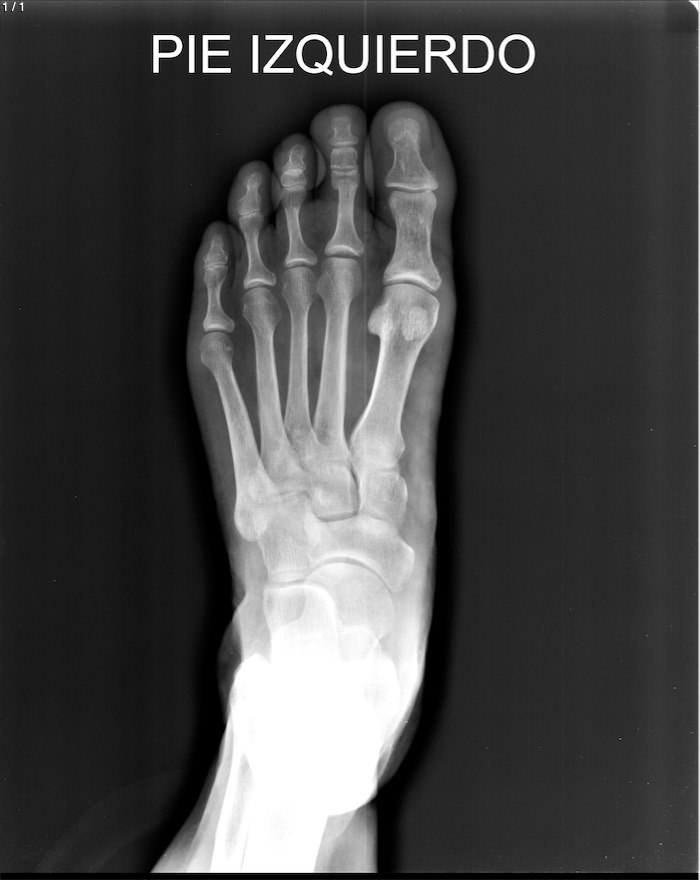

Amelia Guadalupe Ancheyta Bringas - Unnamed